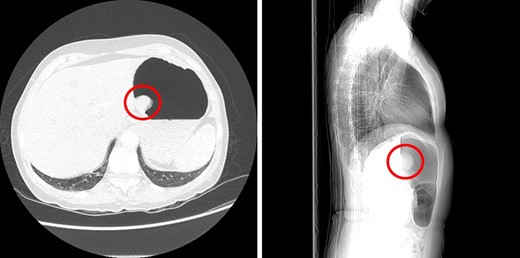

A 68-year-old female underwent a computed tomography (CT) scan of her thorax and abdomen due to the presence of a RET oncogene variant and a history of recurrent tubulovillous polyps of the large bowel. The CT scan showed a 3.7 cm enhancing ‘polyp’ in the lumen of the stomach (Fig. 1) and large hiatus hernia with dilation of the lower oesophagus. Subsequent endoscopic ultrasound showed a lesion suspicious for a GIST located within 2 cm of the OGJ.

Sagittal and axial CT images showing a large polyp on the posterior gastric wall.